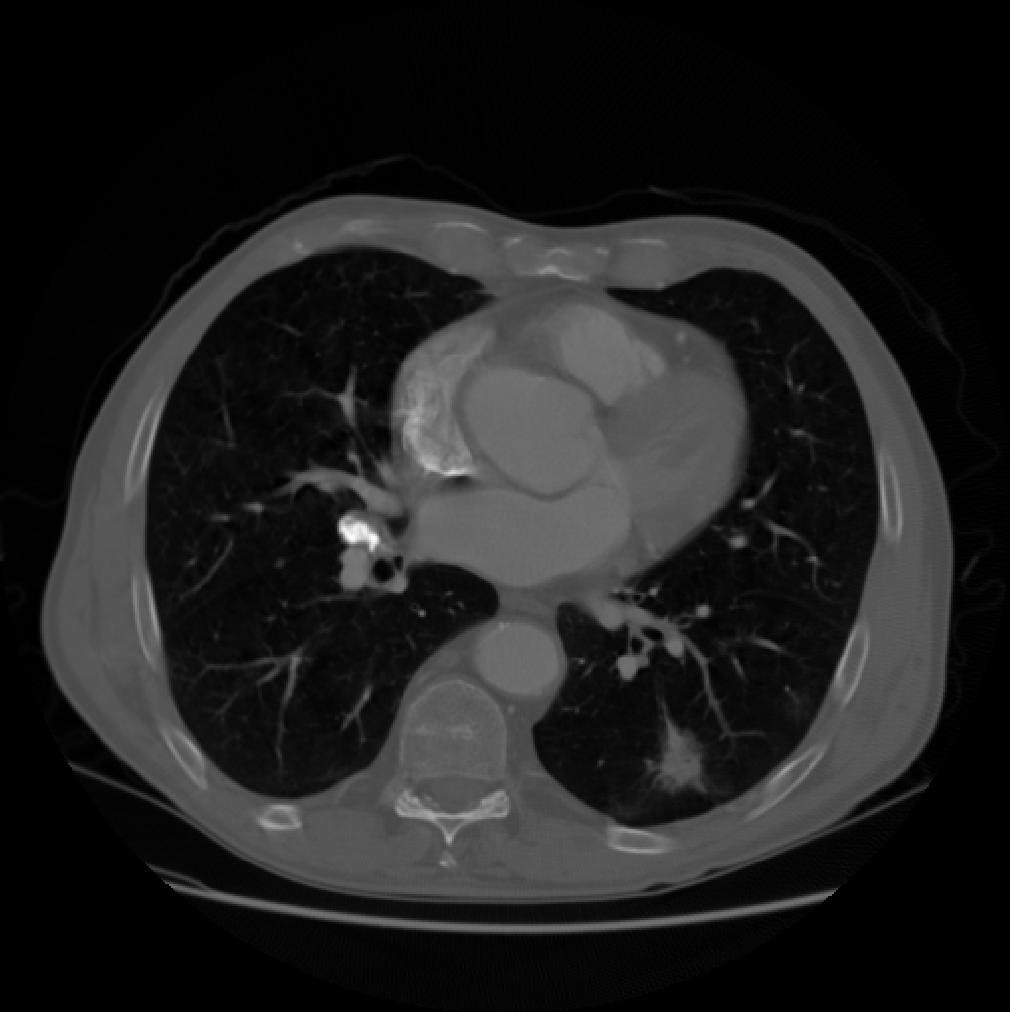

We compare the computation time and SNR of back projection among oblique method, orthogonal method under band limited assumption and box spline methods. We throughly test the performance of oblique method, box spline methods and blurred box spline method (box spline method with detector blur effect). Three images are used in our experiments, the first one consists of randomly placed ellipses, the second one is Forbild head phantom, and the last one is a real CT image from LIDC-IDRI dataset [13] (Fig.2). In our experiments, we fix the sampling steps to be equal in all dimensions, and , where is the downsampling rate. The number of views is set to . Signal to noise ratio (SNR) in dB and structural similarity index (SSIM) are measured for all the methods. All computations were done on one PC (Windows 10 with a 3.7GHz 6-Core Intel Core i7-8700K processors and 32GB of RAM) using Matlab.

(a)

(b)

(c)

Fig.4 shows that our methods provide an improvement over the oblique method in our test cases. Fig.5 shows that our methods are more consistent when the resolution is relatively low. The reason is that oblique method truncates and estimates the sinc function, while we calculate the box spline exactly and have more accurate back projection. Fig.6 shows the absolute total error of the real CT image, the image reconstructed by oblique method suffers from higher error.